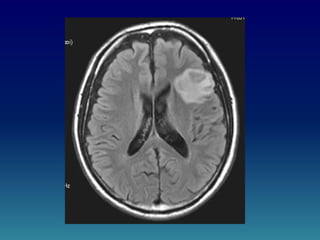

CASO CLINICO

(para primer año)

• MASCULINO DE 32 AÑOS QUE

PRESENTA DESDE HACE 5 MESES

CAMBIOS EN EL ESTADO MENTAL,

EPILEPSIA, CEFALEA Y MALESTAR

GENERAL.

• SE SOMETE AL PACIENTE A

RESONANCIA MAGNETICA

ENCONTRANDO LO SIGUIENTE: